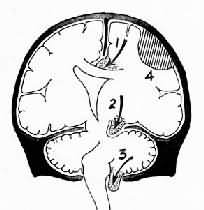

1.扣带回疝又称大脑镰下疝,是因一侧大脑半球特别是额、顶、颞叶的血肿或肿瘤等占位性病变,引起中线向对侧移位,同侧扣带回从大脑镰的游离边缘向对侧膨出,形成扣带回疝。疝出的扣带回背侧受大脑镰边缘压迫形成压迹,受压处的脑组织发生出血或坏死。此外,大脑前动脉的胼胝体支也可受压引起相应脑组织梗死。大脑冠状切面上可见对侧的侧脑室抬高,第三脑室变形,状如新月(图16-6)。

图16-6 脑疝模式图

1.扣带回疝;2.海马钩回疝;3.小脑扁桃体疝;4.硬膜外血肿

2.小脑天幕疝又称海马钩回疝。位于小脑天幕以上的额叶或颞叶内侧的肿瘤、出血、梗死等病变引起脑组织体积肿大,导致颞叶的海马钩回经小脑天幕孔向下膨出。海马钩回疝可导致以下后果:①同侧动眼神经在穿过小脑天幕裂孔处受压,引起同侧瞳孔一过性缩小,继之散大固定,及同侧眼上视和内视障碍。②中脑及脑干受压后移,可导致意识丧失;导水管变狭,脑脊液循环受阻加剧颅内压的升高;血管牵伸过度,引起中脑和桥脑上部出血梗死,可导致昏迷死亡。③中脑侧移,使对侧中脑的大脑脚抵压于该侧小脑天幕锐利的游离缘上,形成Kernohan切迹。严重时该处脑组织(含锥体索)出血坏死,导致与天幕上原发病变同侧的肢体瘫痪,引起假定位症。④压迫大脑后动脉引起同侧枕叶距状裂脑组织出血性梗死(图16-7)。

图16-7 海马钩回疝

左海马回内侧肿胀有深切迹(箭头),中脑右移变形,中脑右大脑脚受压,局部坏死出血(Kemohan切迹)

3.小脑扁桃体疝又称枕骨大孔疝。主要由于颅内高压或后颅凹占位性病变将小脑和延髓推向枕骨大孔并向下移位而形成小脑扁桃体疝。疝入枕骨大孔的小脑扁桃体和延髓成圆锥形,其腹侧出现枕骨大孔压迹(图16-8),由于延髓受压,生命中枢及网状结构受损,严重时可引起呼吸变慢甚至骤停,接着心脏停搏而猝死。

图16-8 小脑扁桃体疝

示小脑切迹,两侧扁桃体疝形成